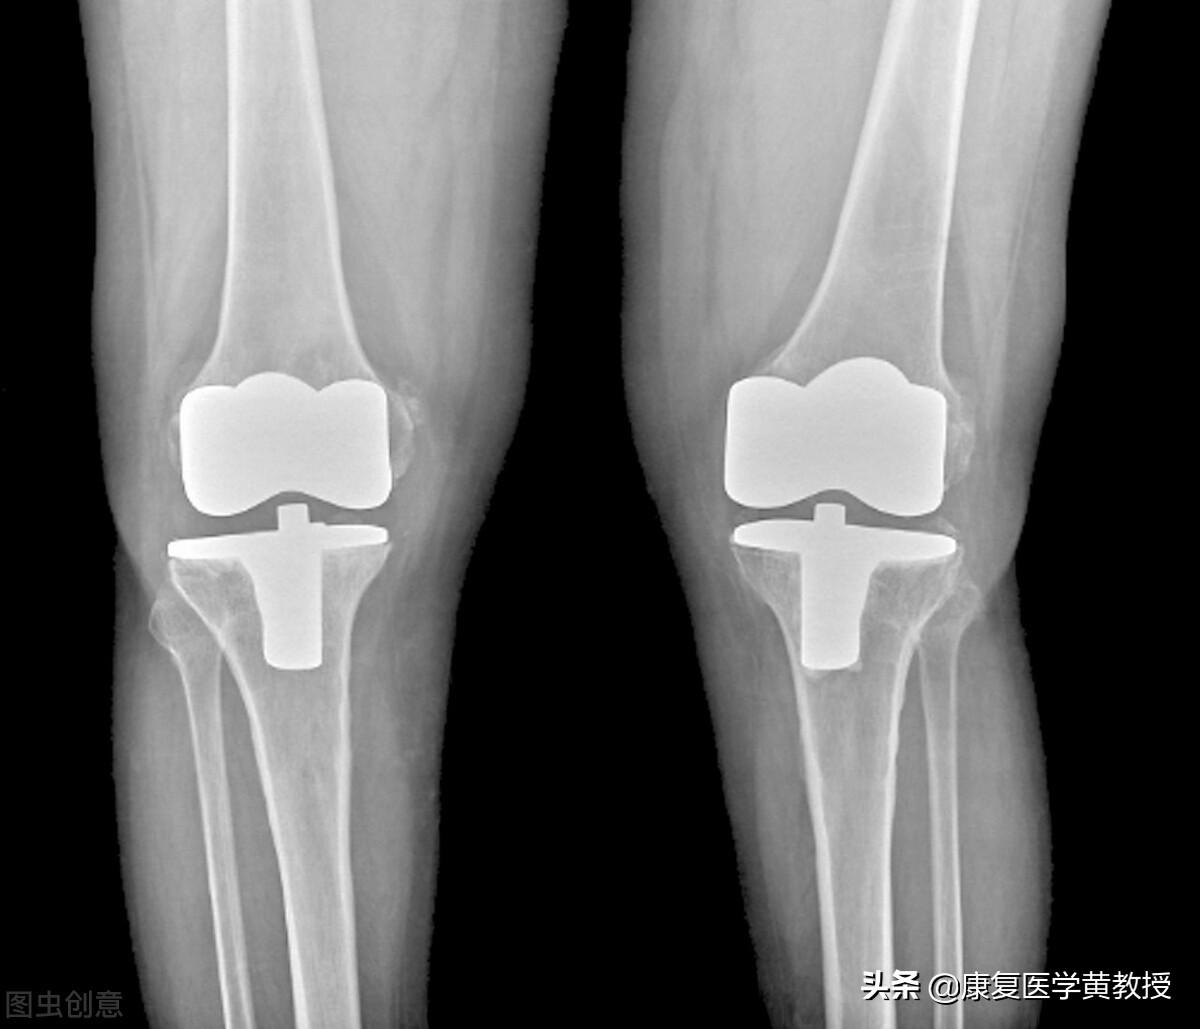

膝关节非常複杂,黄教授不厌其烦地一直发表与膝关节相关的观念与治疗,其实就是希望大家不要等到膝关节疼了才去治疗,因为膝关节一旦出现疼痛,只要去医院做检查,其实膝关节的结构都有程度不一的损伤与破坏,这其中最重要的是 软骨与半月板 ,这两套缓震系统如果失去功能,那麽膝关节就是一步步走入退化的深渊.虽然现在膝关节置换的材质先进,技术也完美,但侵入性治疗其实就是破坏人体的完整性, 因为膝关节发生退变,50%的原因并不在膝关节本身,膝关节置换手术解决的是膝关节结构的问题,但是脊柱,骨盆,髋关节与踝关节, 才是决定膝关节能力的重要伙伴啊!如果问题是踝关节,病变发生在膝关节,你该怎么办??